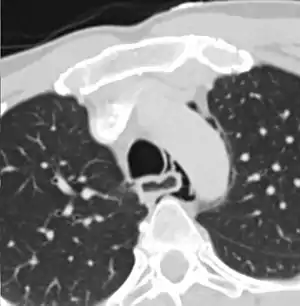

Axial CT image through the upper chest showing extraluminal air (pneumediastinum) surrounding the trachea and esophagus

The diagnosis of Boerhaave's syndrome is suggested on the plain chest radiography and confirmed by chest CT scan. The initial plain chest radiograph is almost always abnormal in patients with Boerhaave's syndrome and usually reveals mediastinal or free peritoneal air as the initial radiologic manifestation. With cervical esophageal perforations, plain films of the neck show air in the soft tissues of the prevertebral space.

Hours to days later, pleural effusion(s) with or without pneumothorax, widened mediastinum, and subcutaneous emphysema are typically seen. CT scan may show esophageal wall edema and thickening, extraesophageal air, periesophageal fluid with or without gas bubbles, mediastinal widening, and air and fluid in the pleural spaces, retroperitoneum or lesser sac.